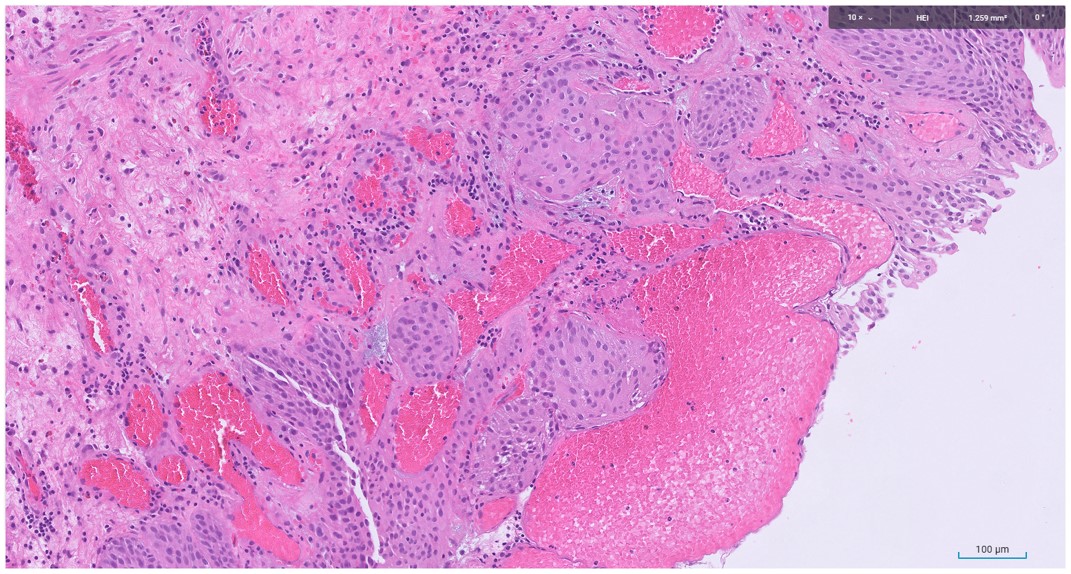

Organ:Bladder

Male in 60s with past history of prostate cancer

Presented with hematuria and obstructive urinary symptoms

Male in 60s with history of prostate cancer

Complaint of hematuria

Microscopic image possibly detecting cancerous areas in human tissue

What is the most likely diagnosis?

1. Radiation cystitis

2. Cystitis cystica

3. Invasive urothelial carcinoma

4. carcinoma in situ

Radiation cystitis